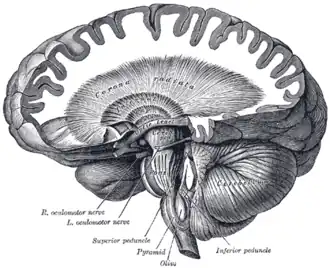

| Cerebellum and basal ganglia | |

Neuroferritinopathy is a genetic neurodegenerative disorder characterized by the accumulation of iron in the basal ganglia, cerebellum, and motor cortex of the human brain. Symptoms, which are extrapyramidal in nature, progress slowly and generally do not become apparent until adulthood.[1] These symptoms include chorea, dystonia, and cognitive deficits which worsen with age.[2][3]

These mutations result in decreased iron-binding ability.[1] The oxidative damage caused by increased iron leads to apoptosis, or programmed cell death.[1] Accumulation of iron in the brain is extremely dangerous as excess iron catalyzes the formation of free radicals, which have damaging effects to the brain.[1] The iron accumulation characteristic of neuroferritinopathy particularly affects the cerebellum, basal ganglia, and motor cortex regions of the brain.[1]

The concentration of iron in a healthy brain varies greatly from region to region. The specific regions of the brain that are associated with motor functions appear to have larger accumulations of iron than non-motor-related regions. This observation of varying iron concentrations is a possible explanation for the correlation between movement disorders and the iron imbalance within the central nervous system.[3]

Neuroimaging

Neuroferritinopathy is most commonly diagnosed using MRI and other neuroimaging techniques.[1] MRIs help identify the iron deposits in the cerebellum, basal ganglia, and motor cortex common to neuroferritinopathy.[8] MRIs of affected individuals also show mild cerebellar and cerebral atrophy, or tissue breakdown, and gas cavity formation in the putamen.[8] Most importantly, the MRIs show misfolded ferritin proteins and iron deposits in the glial cells of the caudate, putamen, globus pallidus, cerebral cortex, thalamus, and purkinje cells, causing neuronal death in these areas.[8]